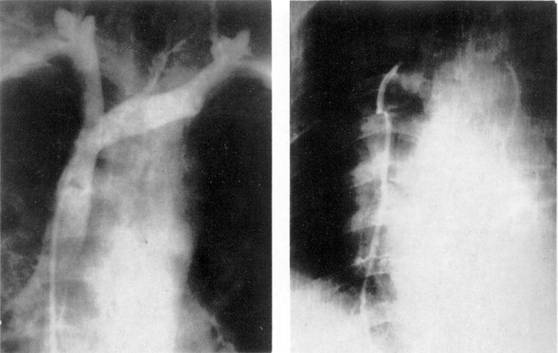

При селективной ангиографии бронхиальных артерий катетер вводится в грудную аорту и далее — до устья бронхиальных сосудов; введение контрастного вещества осуществляется с помощью автоматического инъектора. Сериография, проводимая, как правило, в переднезадней проекции, может быть дополнена рентгенограммами в боковой или косой проекциях в зависимости от задач исследования (рис. 7).

При анализе бронхиальных ангиограмм определяются уровень и тип анатомического ветвления сосудов, положение, форма, диаметр, характер контуров сосуда, извитость его и проходимость, характер и уровень окклюзии, степень развития коллатеральных ветвлений и их взаимосвязь с легочной артерией. Учитываются уровни анастомозирования двух систем кровообращения легких (субсегменты, сегменты, доли или